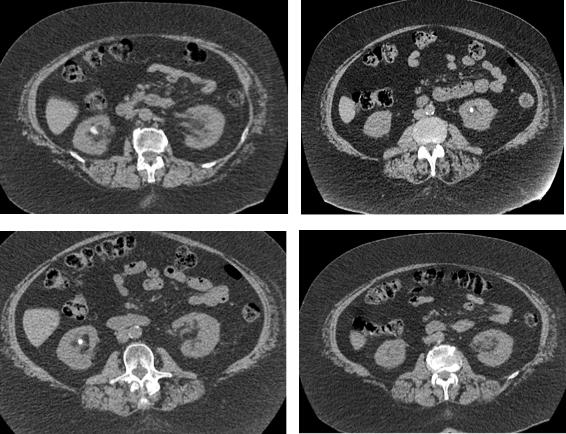

Funding: None

Authors’ contributions: M A A D , W D C M , A M T

Acknowledgments: None

REFERENCES